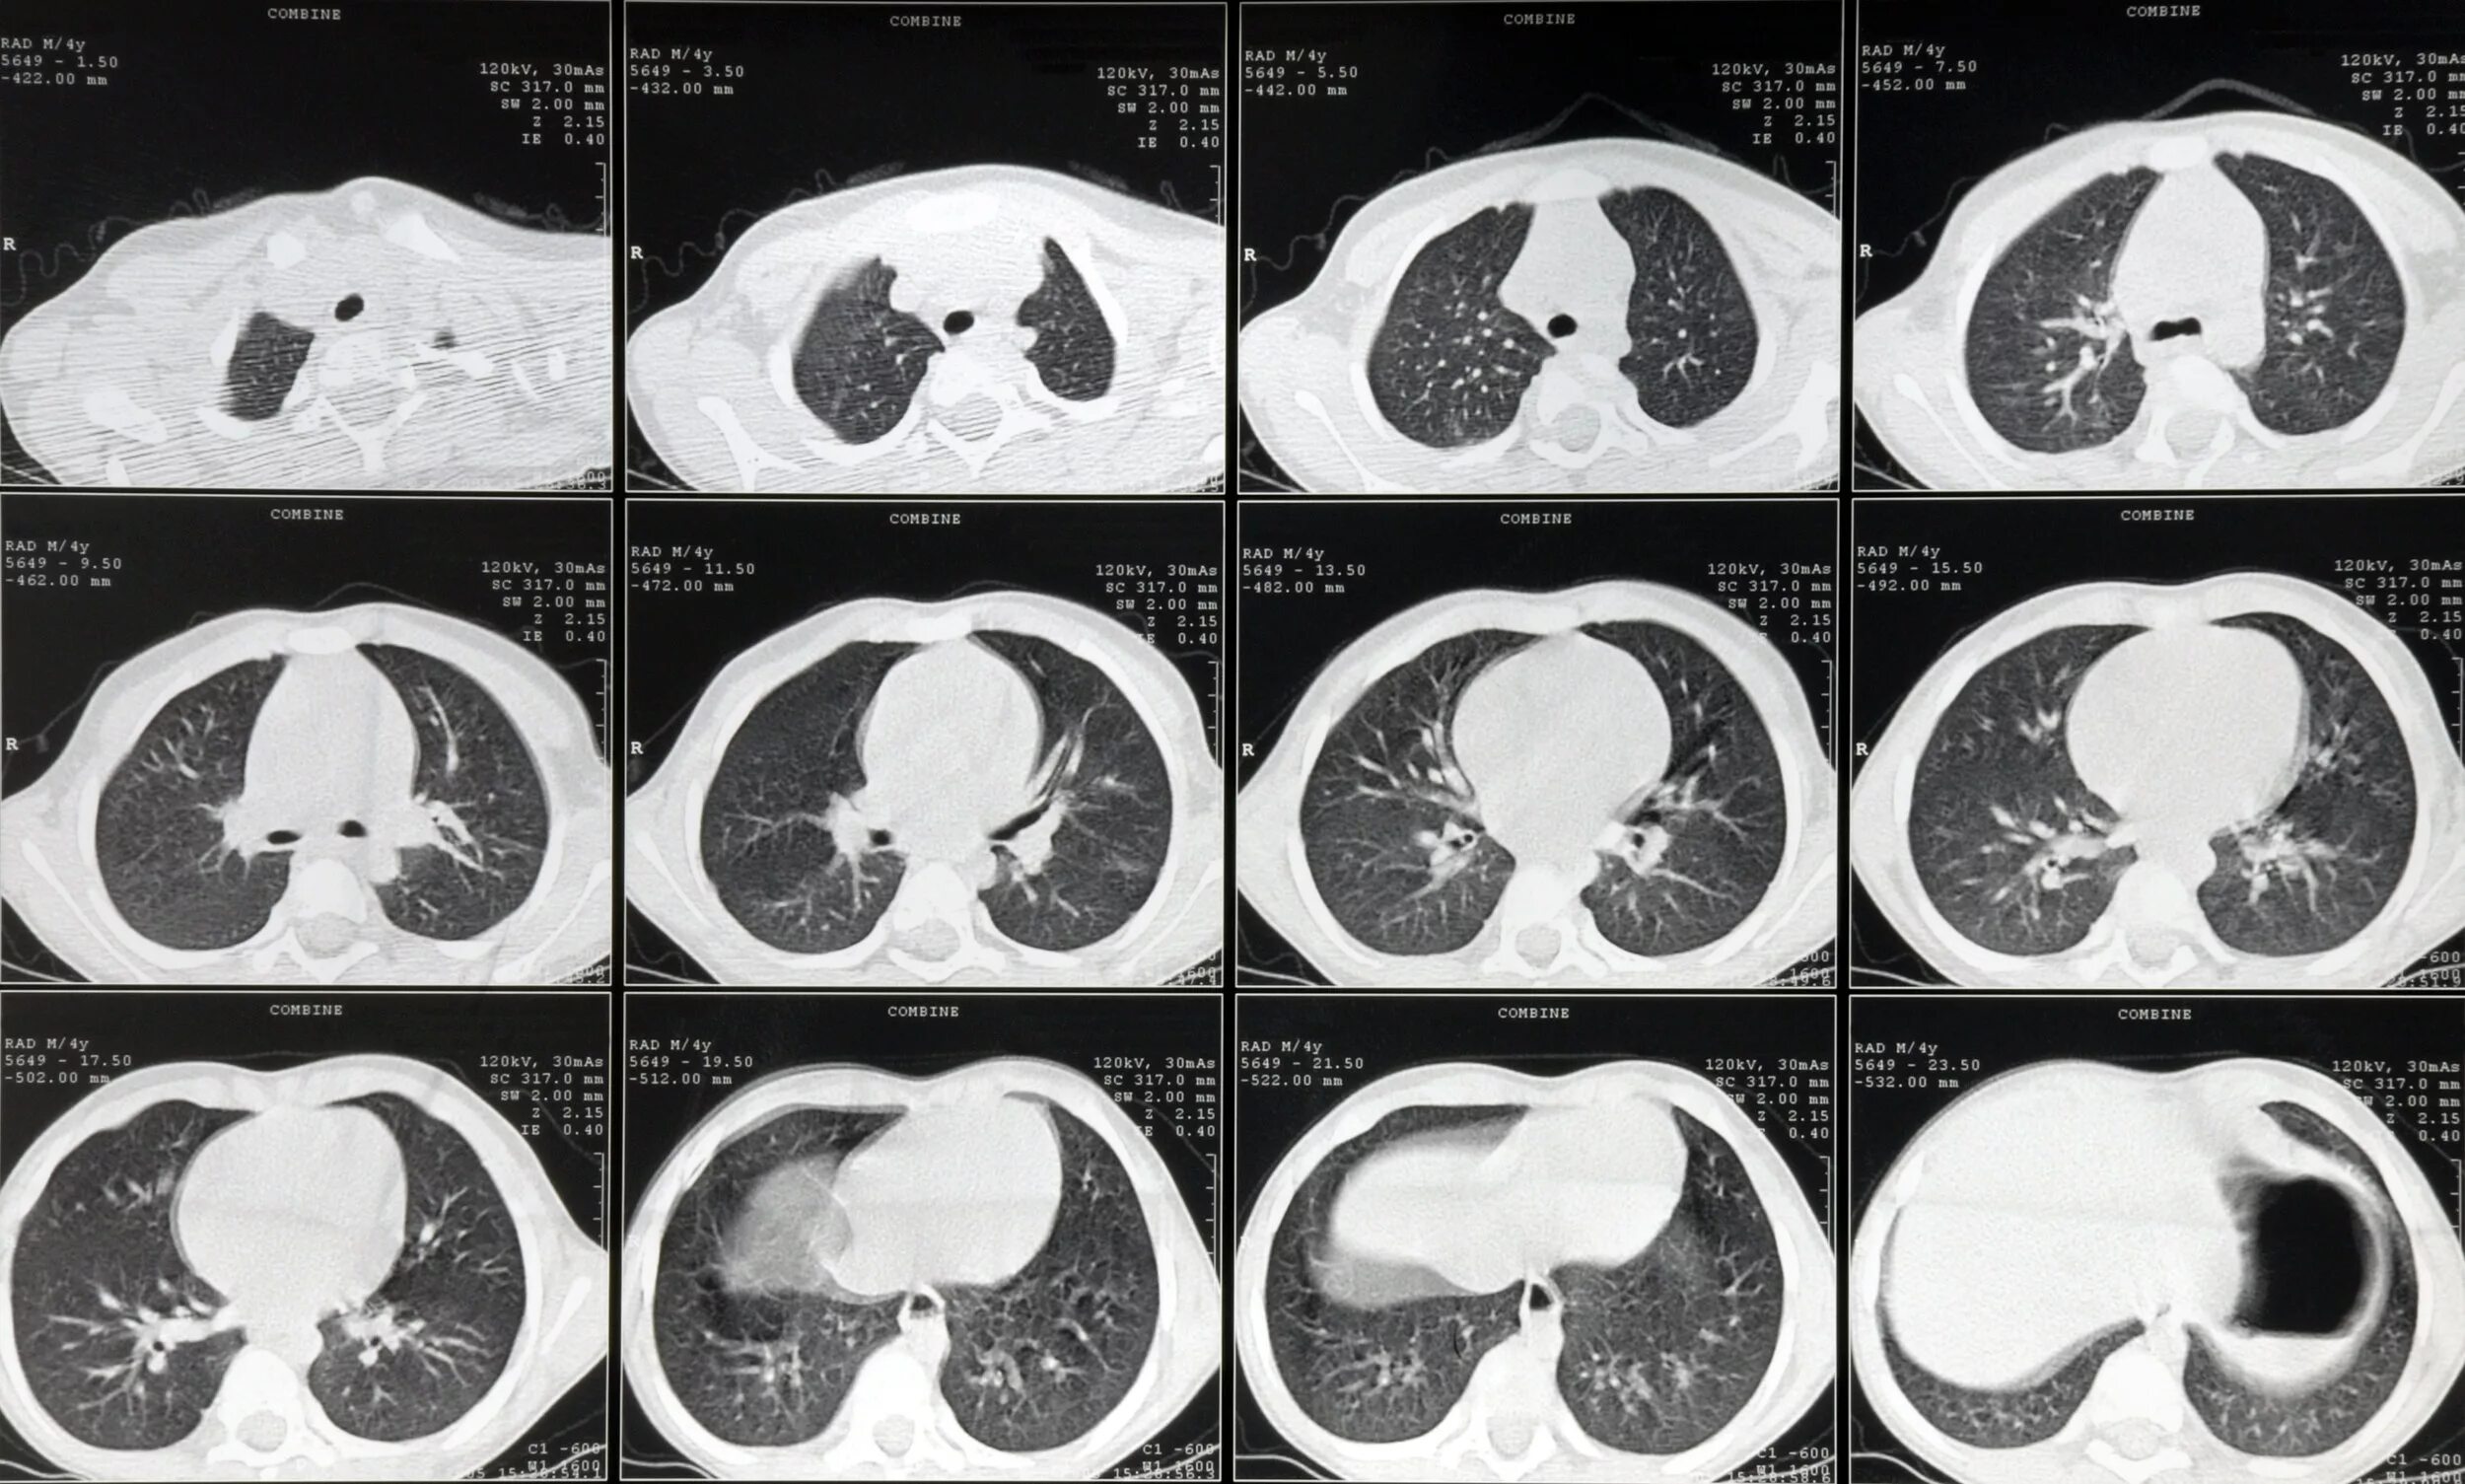

Что такое с кт